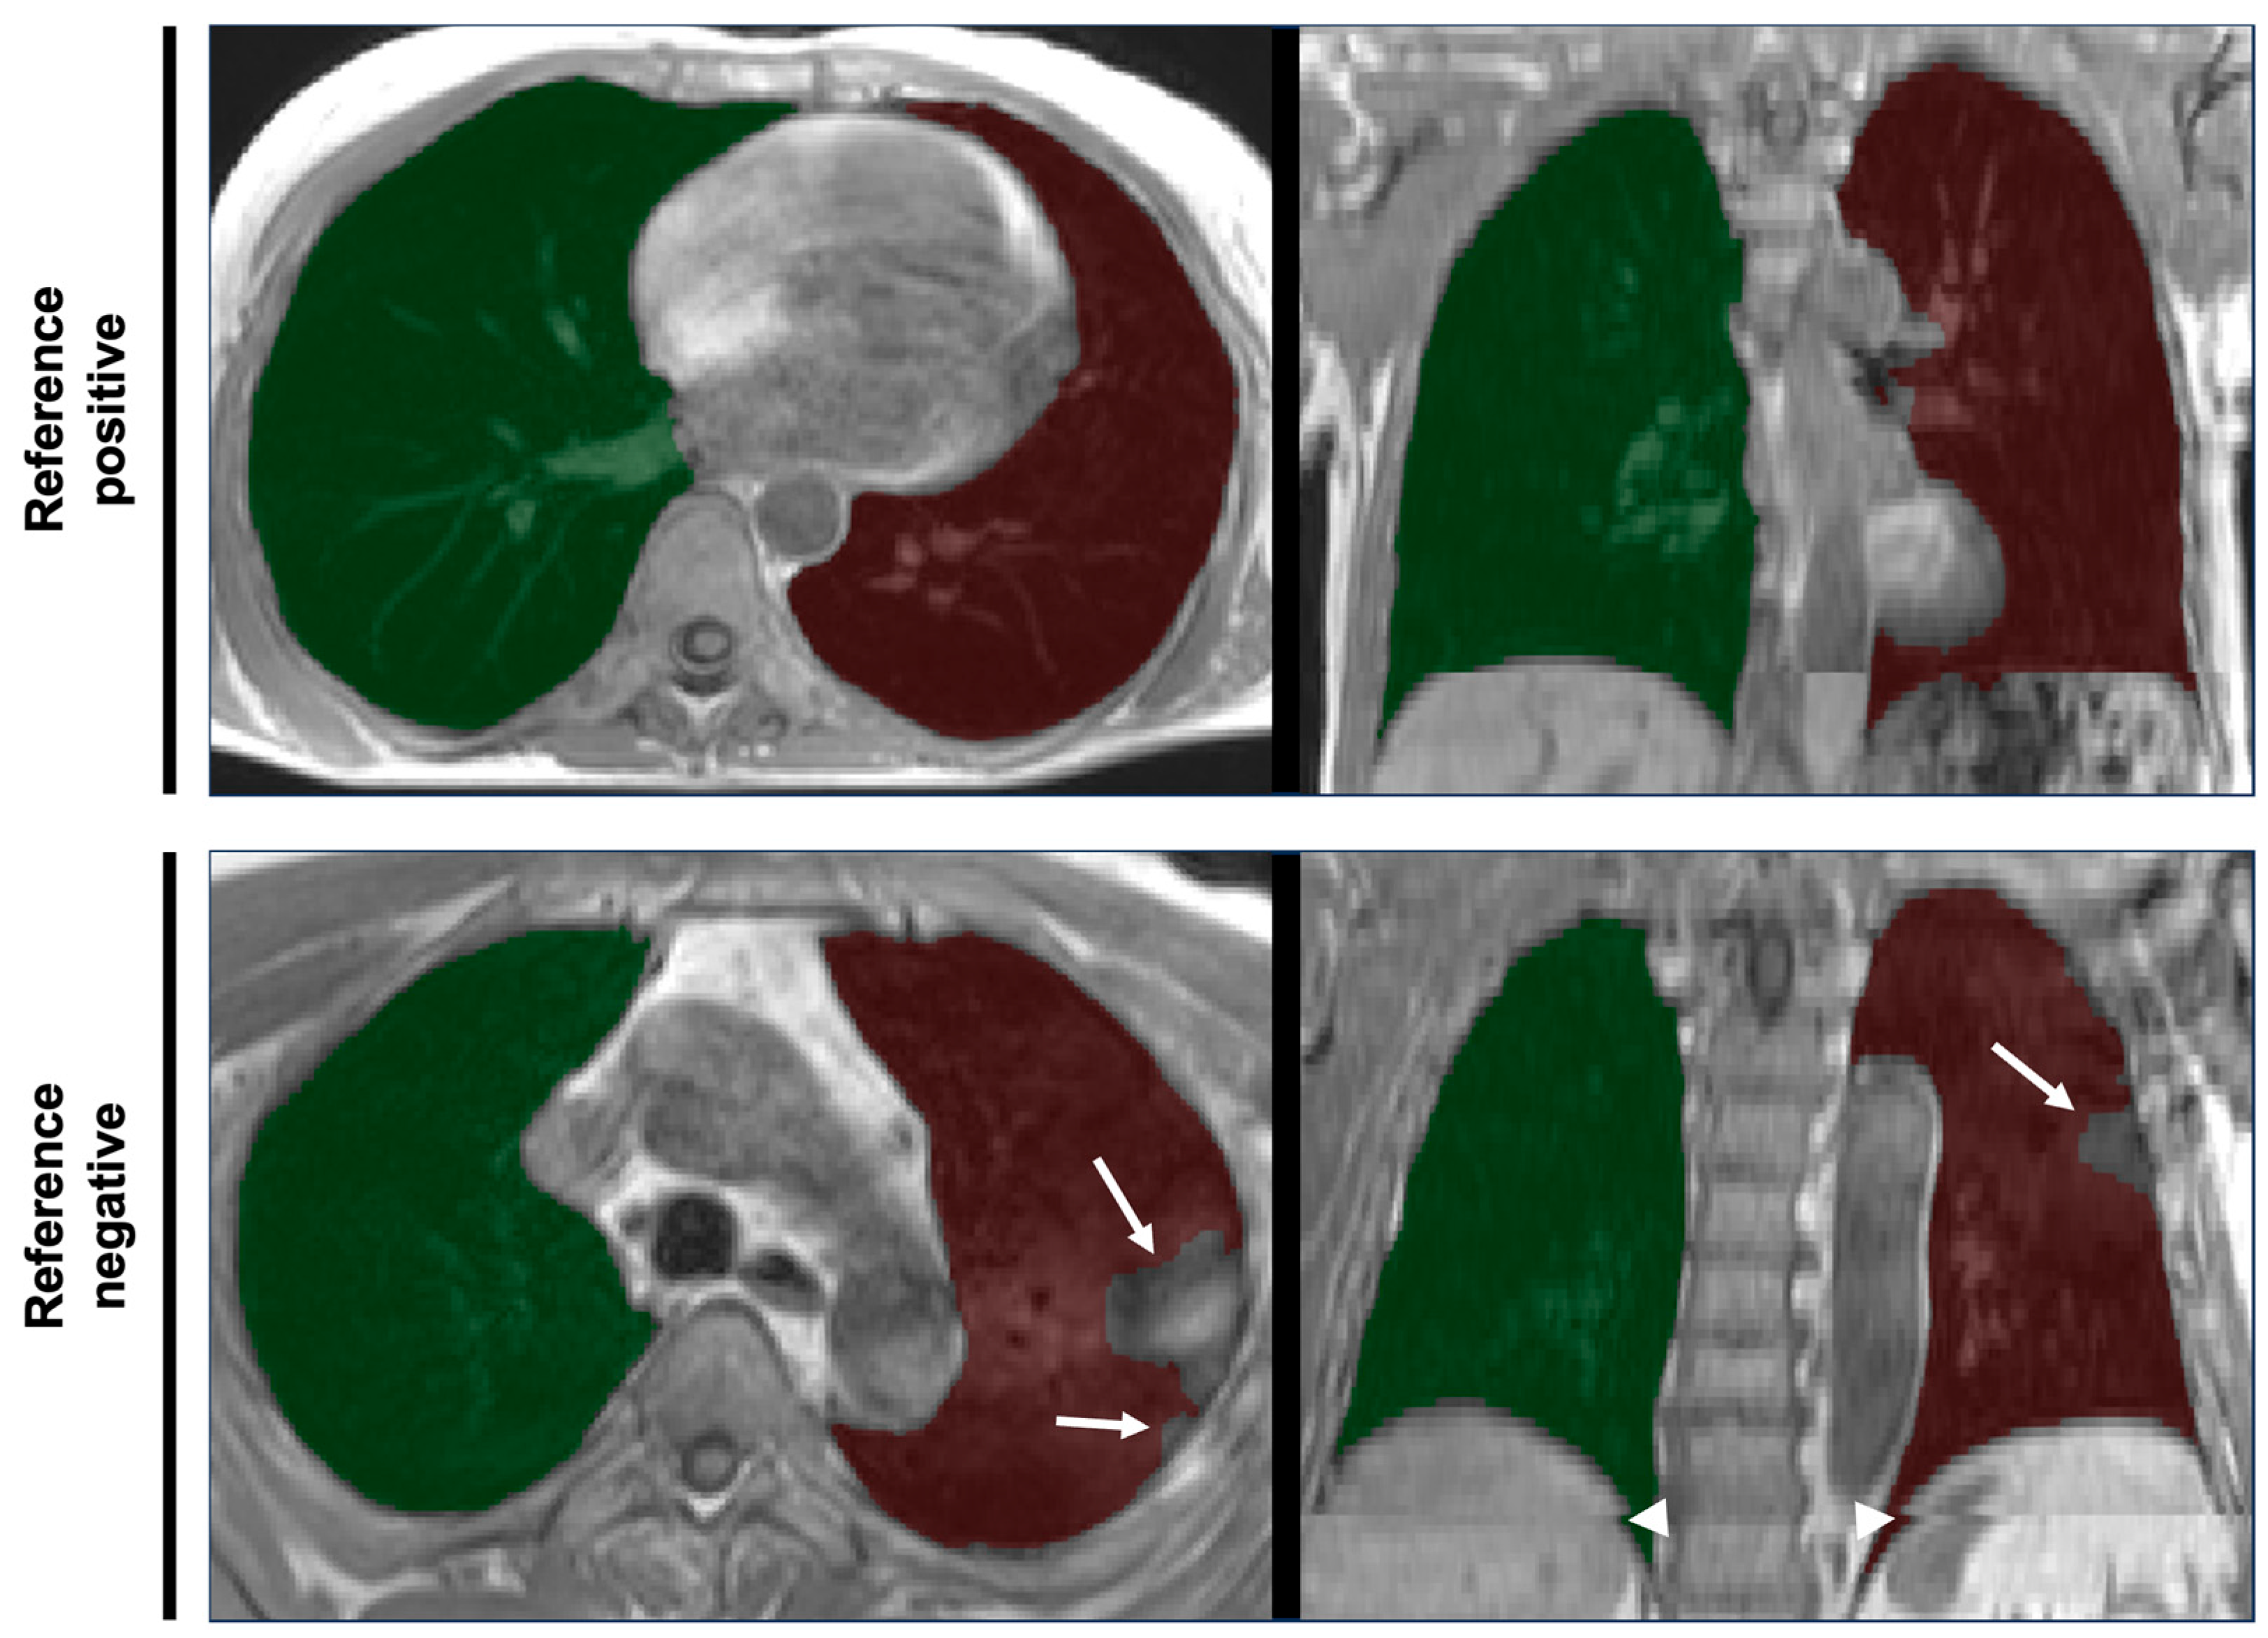

Figure 1. Examples of thoracic MRI data and overlying lung segmentation masks. Axial slices (left column) and coronal views (right column) of the thoracic part of axially acquired T1-weighted 3D VIBE two-point DIXON images of thorax and abdomen of two different participants of the NAKO study. Translucent overlays of right (green) and left (red) lung segmentation masks as results of deep learning-based automated segmentation are shown. The quality of the lung segmentation of the participant in the top row was deemed sufficient for further analysis (reference positive). The bottom row shows an example of erroneous segmentation according to the reference standard (reference negative). Note the exclusion of consolidated parts of the lungs (arrows) and the spatial inconsistencies (composing artifacts, arrowheads) resulting from the stitching of separate acqusitions for the lower and upper part of the scan volume.